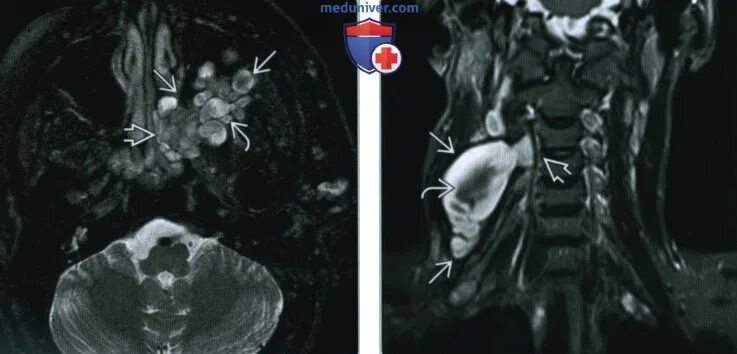

Нейрофиброматоз мрт